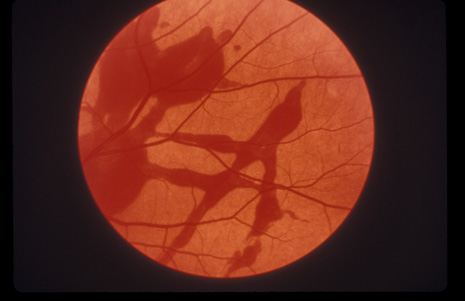

COMMOTIO RETINAE

Commotio retinae (Latin, meaning retinal contusion) is a contrecoup injury. It can occur peripherally (Fig. 8) or centrally, in which case it is called Berlin's edema (Fig. 9). Immediately and for several hours after the trauma, the retina appears normal, although the patient may complain of decreased vision. Thereafter, the outer layers of affected retina become opaque. On fluorescein angiography, the opaque retina blocks background choroidal fluorescence, and in most cases there is no leakage into or under the retina (Fig. 10). For years, clinicians had difficulty explaining this blockage, because leakage is expected in conditions with edema. It was then shown in experimental animals and in human autopsy eyes that Berlin's edema is not true edema. The retinal opaqueness is the result of intracellular edema and fragmentation of the photoreceptor outer segments and intracellular edema of the underlying pigment epithelium. There is little or no intercellular fluid.66–69

Fig. 8. Peripheral commotio retinae. The retinal blood vessels are clearly seen because the retinal whitening is in the outer retinal layers.

The visual acuity in commotio retinae varies from 20/20 to 20/400 and does not always correlate with the degree of retinal opacification. There is no known treatment. The prognosis is usually excellent except in cases with associated subfoveolar choroidal rupture and in cases with choroidal rupture with subfoveolar hemorrhage. Poor visual recovery can also be expected in cases with severe retinal pigment epithelial damage. Serous retinal detachment (Fig. 11) signals this condition, which can be confirmed by leakage of fluorescein into the subretinal space.70